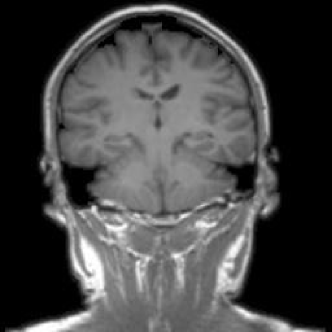

4.1.6 Brain MRI

Brain tumors pose significant health challenges, often impacting critical functions such as vision, balance, and cognition. Early detection is crucial for improving patient outcomes and quality of life. Through MRI scans, different conditions of the brain can be visually detected. The selected brain tumor dataset 666https://www.kaggle.com/datasets/sami009mr/brain-tumor-dataset contains 3,362 images across four categories: glioma, meningioma, pituitary tumors, and normal brains. Images illustrating the three aforementioned classes can be found in Fig. 7.

Refer to caption

(a) No tumor

(b) Glioma tumor

(c) Meningioma tumor

(d) Pituitary tumor

Figure 7: Brain MRI scans.